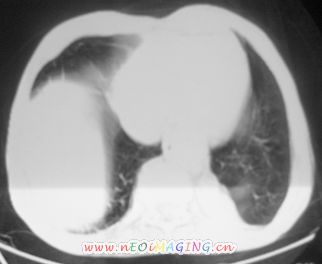

以下是引用卜一在2007-10-7 9:38:00的发言:[br]左下肺胸膜下团片影,内见含气支气管像,临近胸膜未见增厚。多考虑:1 左下肺炎症,建议消炎后复查!2 不除外肺隔离症合并感染!